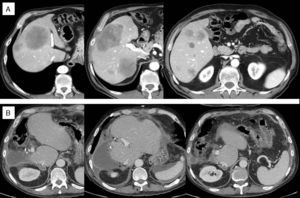

A) TAC inicial: múltiples metástasis de 1 a 10cm en segmentos derechos y segmento IV, una metástasis en segmento II y 2 en segmento III, superficiales de 0,5-1cm y segmento I libre de enfermedad. Nódulo pulmonar inespecífico de 0,5cm. B) TAC postoperatorio: ausencia de enfermedad hepática.

Varón de 68 años con adenocarcinoma en ángulo esplénico de colon no estenosante y sin signos de sangrado. Metástasis hepáticas múltiples bilobares potencialmente resecables. CEA inicial: 344, K-ras mutado. La figura 1A muestra las imágenes del TAC inicial. Tras 10 ciclos de FOLFOX/bevacizumab, sin respuesta RECIST, apreciamos que existía respuesta morfológica, y consideramos la posibilidad de resección quirúrgica. El VHR para una resección R0 era de 18% (240cc, peso 80kg). La embolización portal del segmento IV no era posible por la gran metástasis presente en el mismo, que amputaba las ramas portales de dicho segmento impidiendo la colocación de coils. Consideramos la técnica ALPPS, pero pensamos que el riesgo de complicaciones a nivel del segmento IV, debido a la elevada carga tumoral, y el riesgo de insuficiencia hepática por el bajo volumen residual, eran altos, y nos decidimos por realizar la técnica que describimos a continuación:

La TAC de reevaluación poscirugía, mostraba ausencia de metástasis hepáticas (fig. 1B), un nódulo pulmonar de 1cm y otros 2 nódulos subpleurales subcentimétricos de nueva aparición. Se reinició tratamiento con quimioterapia sistémica con progresión de la enfermedad pese a las diferentes líneas de tratamiento administradas.